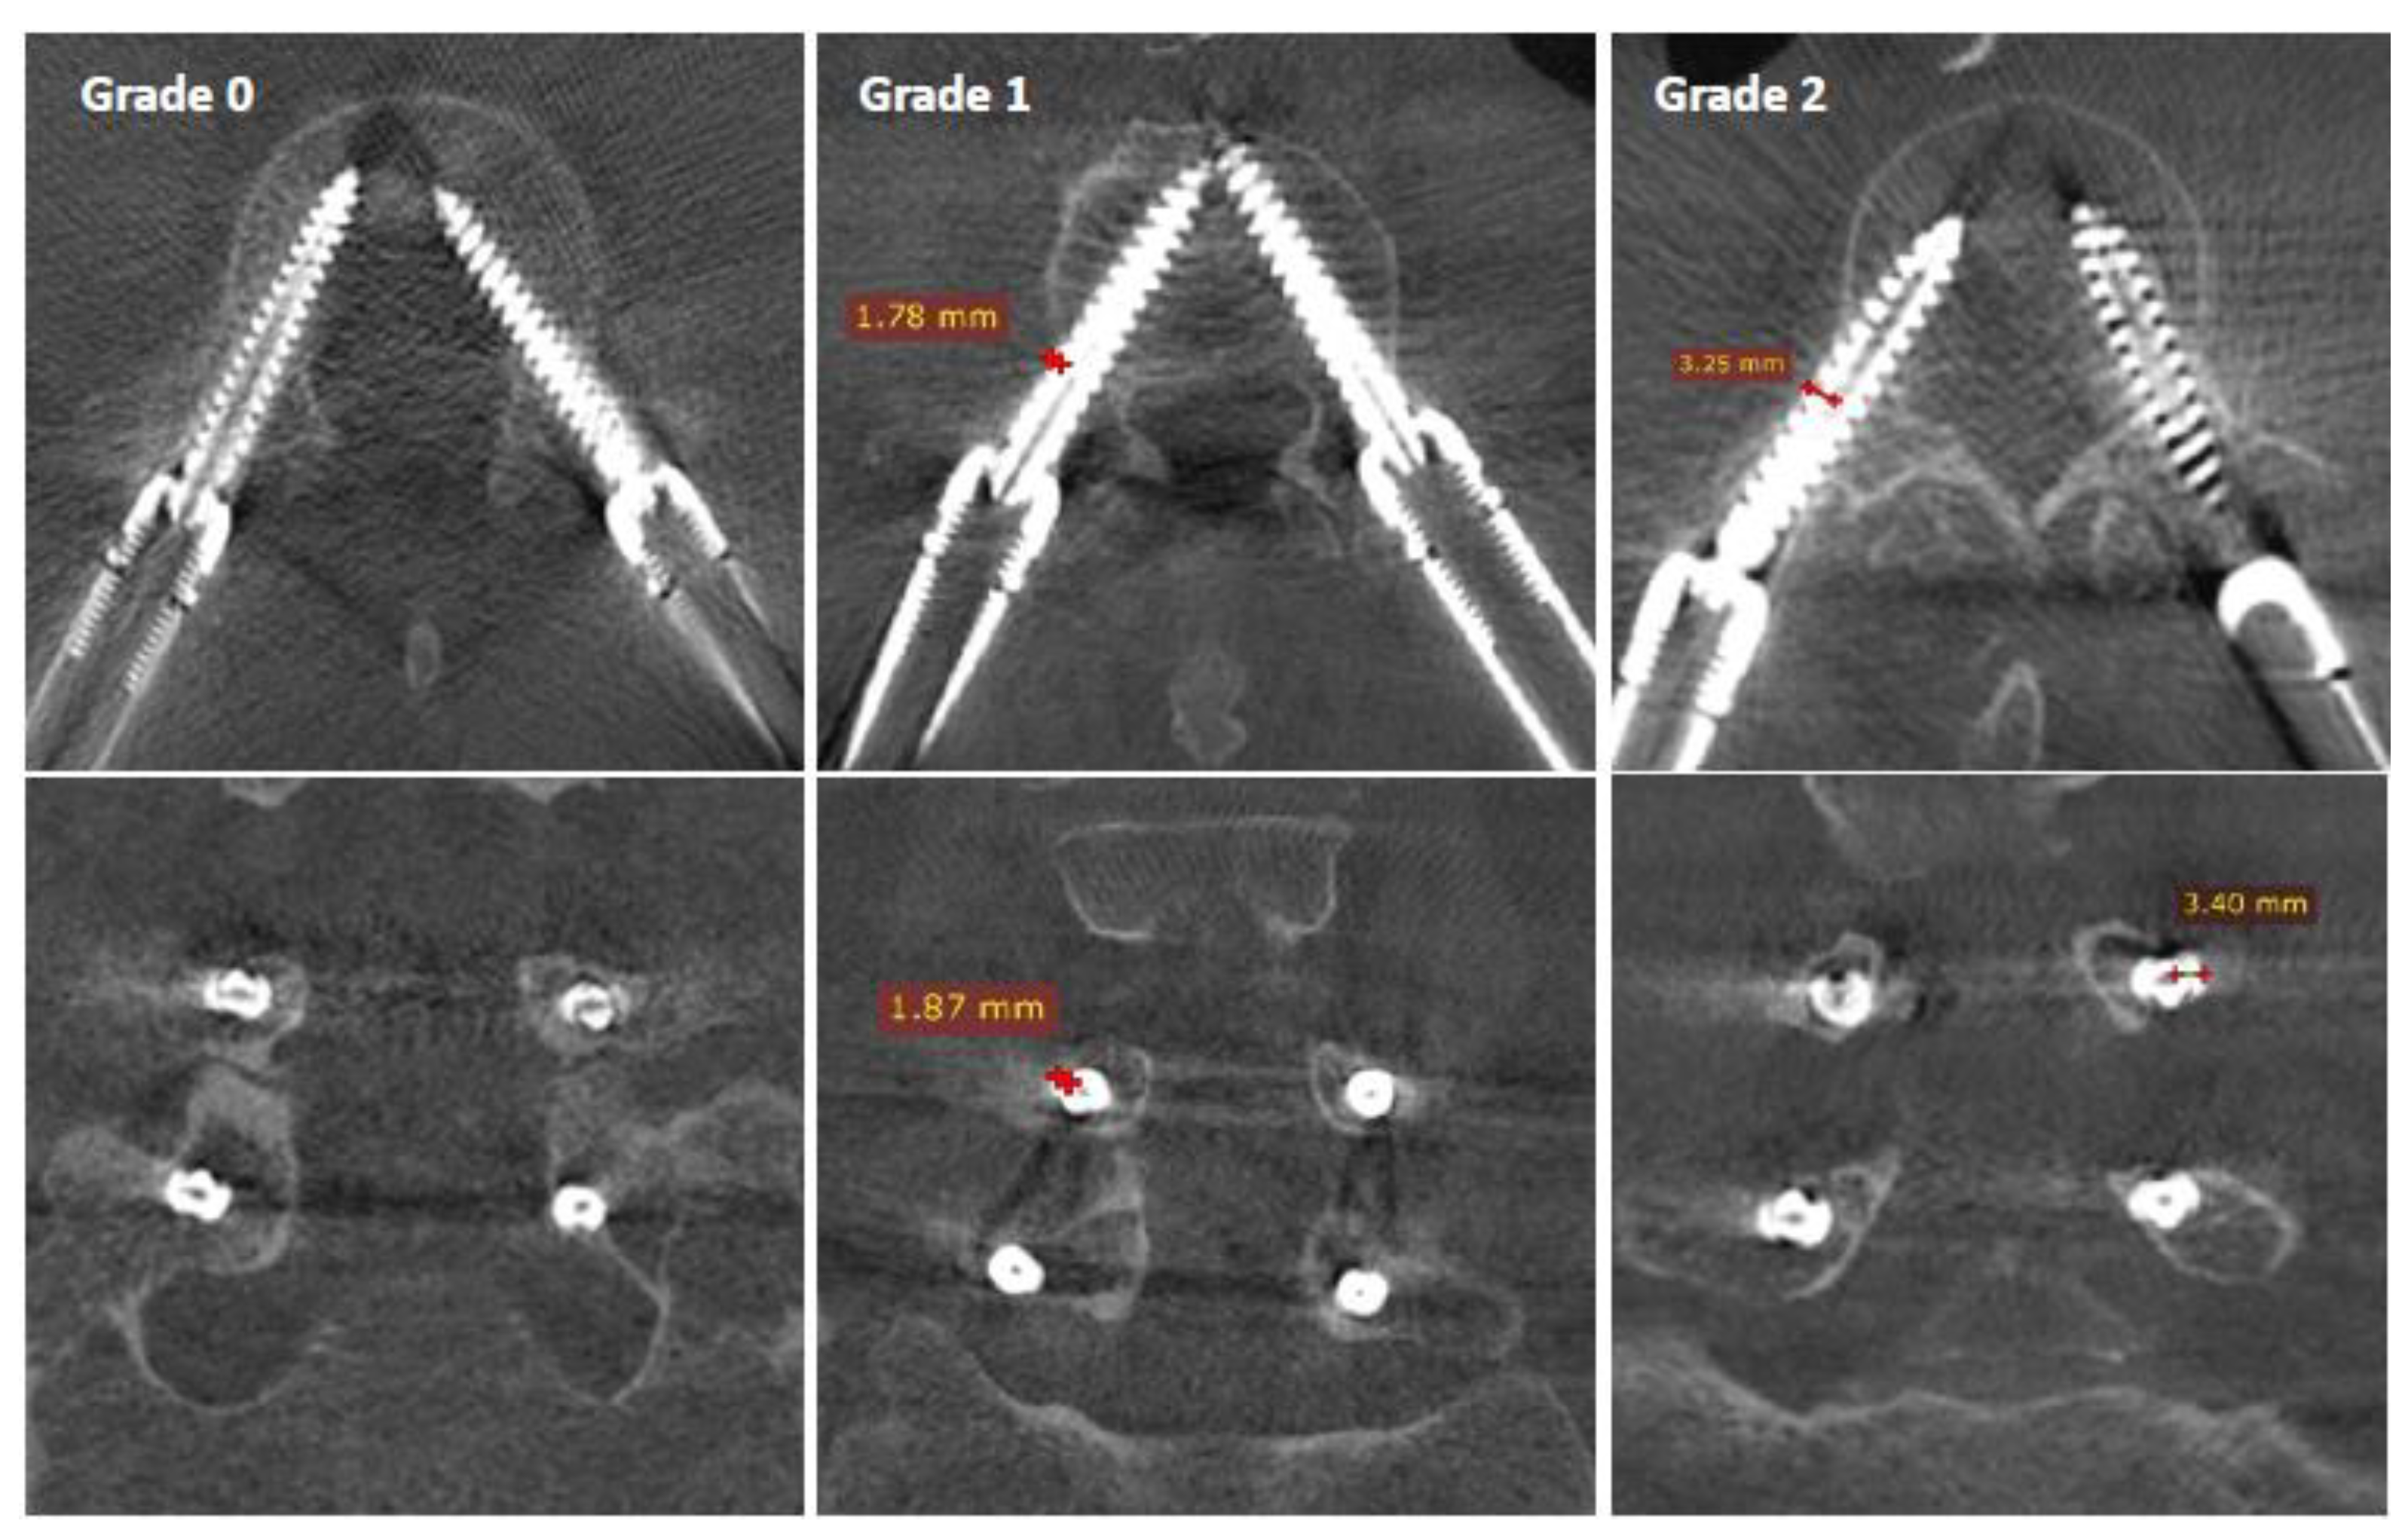

The screw diameter of 6.5 mm was used as a scale, which enabled the measurement of cortical breaches on axial and coronal views of each pedicle, as demonstrated in Figure 3.

Figure 3.

Screw placement accuracy with the pedicle according to Gertzbein and Robins: Grade 0 is perfectly contained within the pedicle, Grade 1 represents a cortical encroachment <2 mm, and Grade 2 is a breach between 2 and 4 mm.